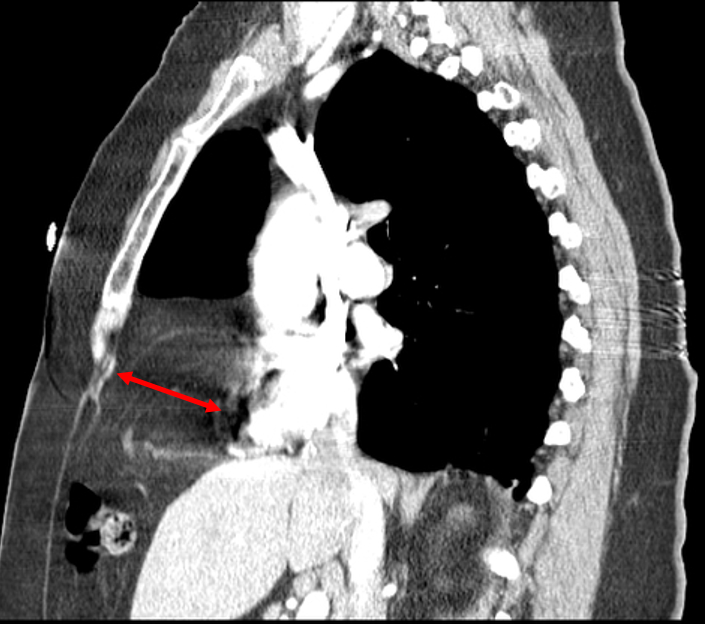

A congenital diaphragmatic hernia is a birth defect that involves the diaphragm, a muscle underneath the lungs that divides the chest cavity from the abdominal cavity. In a situation involving fetal malformation of the diaphragm, the dangers involved pertains to improper lung development or a situation where the abdominal organs push up into the chest cavity. So a congenital diaphragmatic hernia treatment before birth is ideal.